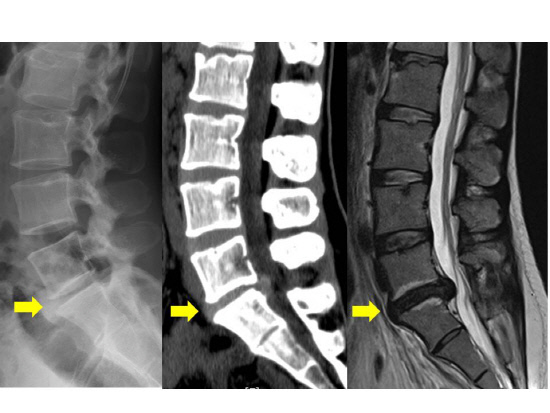

두 번째 증상으로는 다리로 방사되는 통증, 즉 방사통이 있습니다.

허리에서 시작된 통증이 엉덩이와 다리로 퍼지는 경우가 많으며, 이는 디스크가 신경을 압박하기 때문입니다.